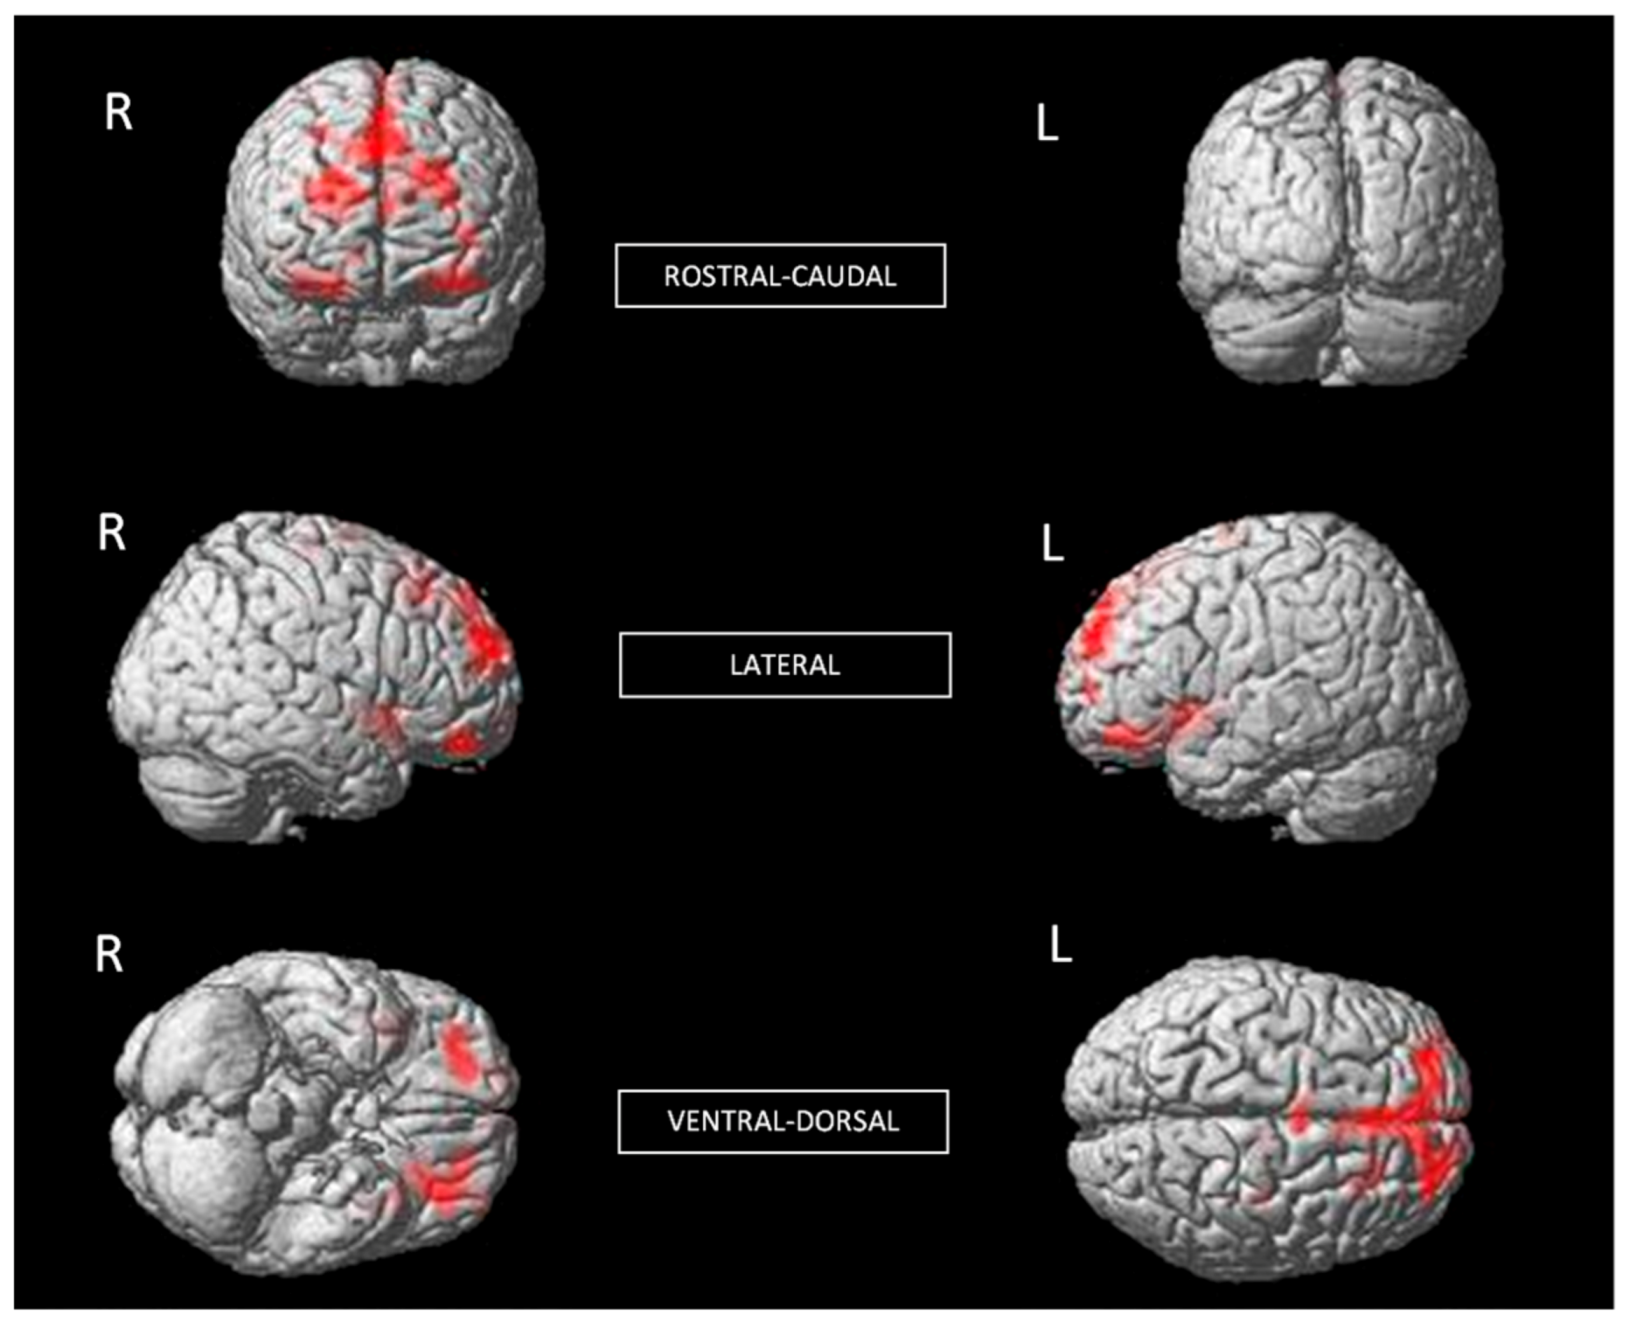

Additionally, individuals with phobia showed a larger GMV in the left putamen than non-fearful controls (t (60) = 3.48, p < 0.001) (Table 1 and Figure 2), with a moderate effect size. The putamen is related to complex motor regulation and the facilitation of different types of learning.

Figure 2. Significant differences in GMV of the putamen between individuals with phobia (larger) and non-fearful controls (corrected with Gaussian random field theory with a significance threshold of a voxel-wise value of p < 0.001 and cluster probability of p < 0.05). T-score is represented on a color bar.